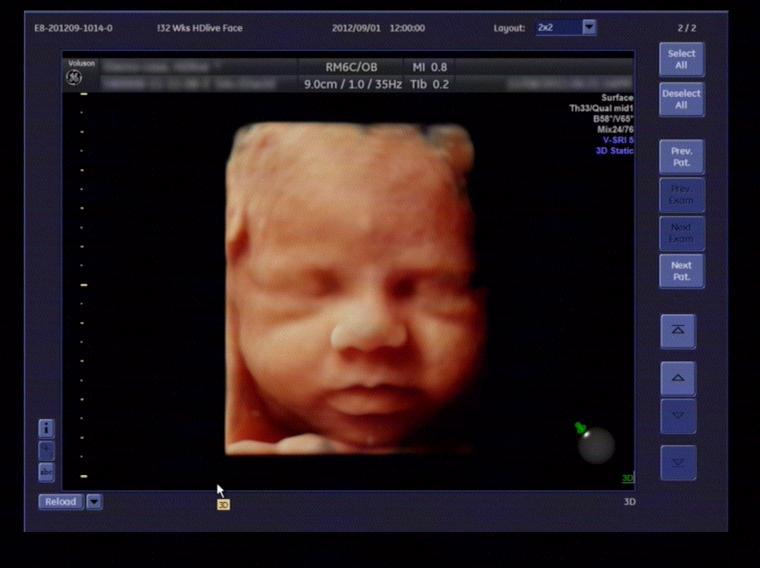

四維與三維彩超的區(qū)別:四維彩超也稱為實(shí)時三維彩超,三維彩超是靜態(tài)的,只能是某個時間點(diǎn)上的照片,四維彩超是動態(tài)的,就是在三維圖像上加上時間軸,顯示隨著時間變化而變化的立體圖像,能夠顯示未出生的寶寶的實(shí)時動態(tài)活動圖像,如打哈欠、伸懶腰、吮手指等等奇妙的動作,所以四維看起來會更清楚明晰。